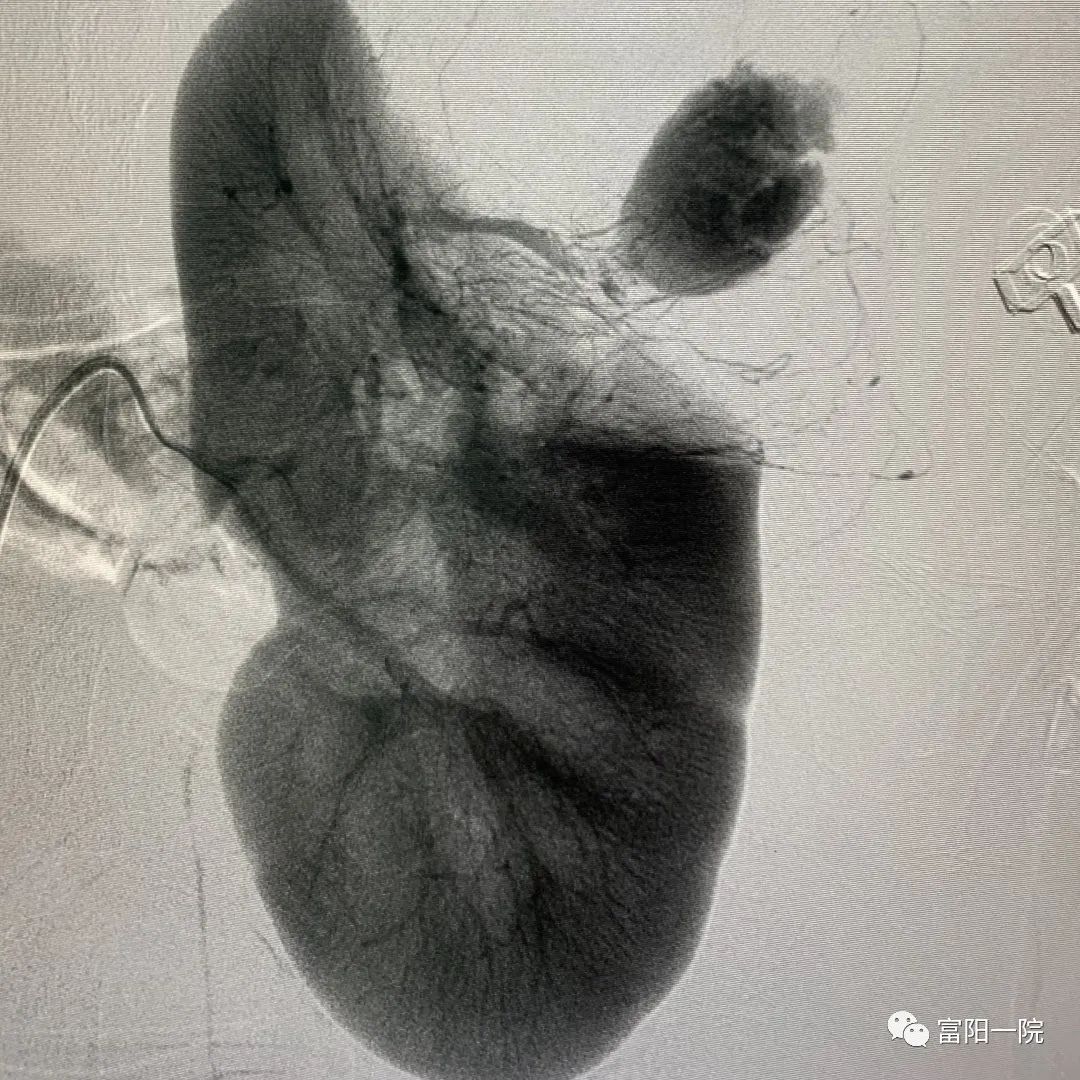

“元凶”很有可能就是左侧肾脏错构瘤破裂出血。经腹部增强CT检查,结果提示“左肾错构瘤破裂出血考虑,左肾周围巨大血肿”,这印证了专家团队的猜测。

诊断基本明确,那如何保护“母子平安”?产科、血管外科、泌尿外科等多位专家讨论后,迅速制定下一步治疗方案——介入栓塞止血治疗。

医院普一(甲乳疝、血管外科)科副主任欧阳勇执行介入操作,产科主任孙素芳监测胎儿情况,产科团队、麻醉团队、监护室团队、儿科团队、泌尿外科团队随时待命。

十余分钟内,局麻、穿刺股动脉植入动脉鞘,置入一根1.5米泥鳅导丝……欧阳勇迅速找到肾错构瘤破裂出血责任血管,成功将小莉从“死神”手中拉回。